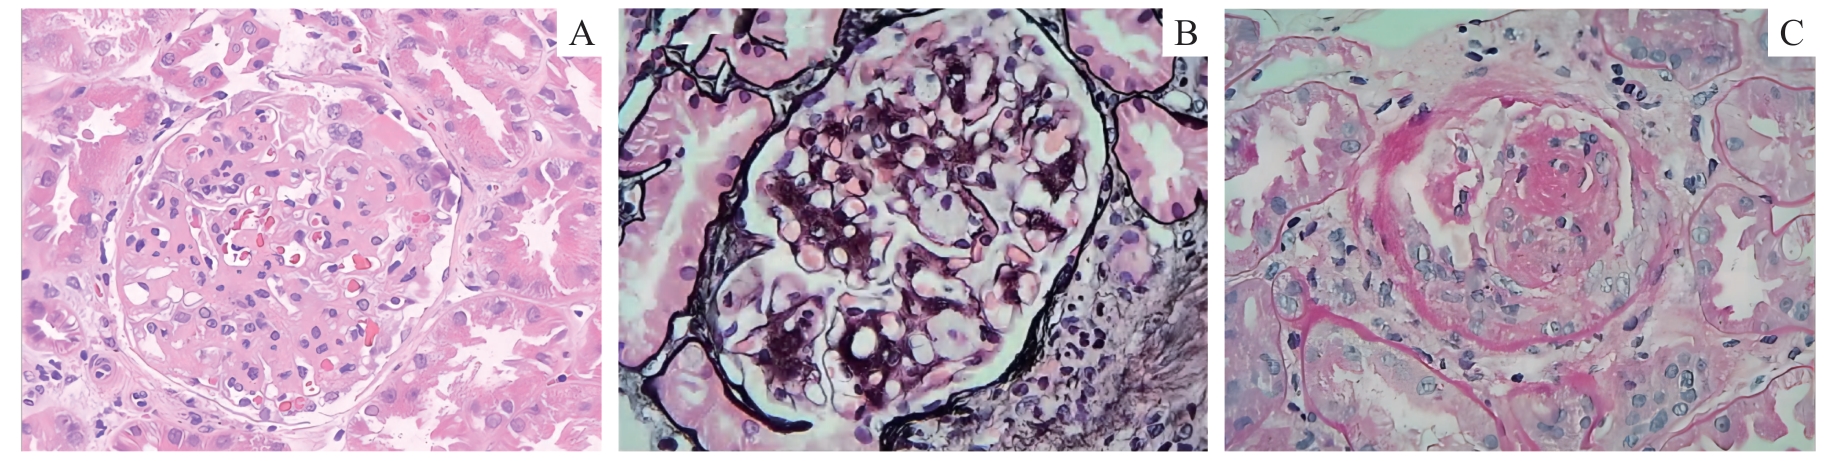

| 图1 光学显微镜下观察肾脏组织(×400) Note: A/B. Hematoxylin-eosin (H-E) staining (A) and periodic acid-silver methenamine (PASM) staining (B) show mesangial cells and stroma with moderate to severe hyperplasia, thickening of the basement membrane, segmental mesangial insertion, and “double track sign” formation. C. Periodic acid schiff (PAS) staining show microcytic crescent formation. |

| Fig 1 Observation of renal tissue under an optical microscope (×400) |